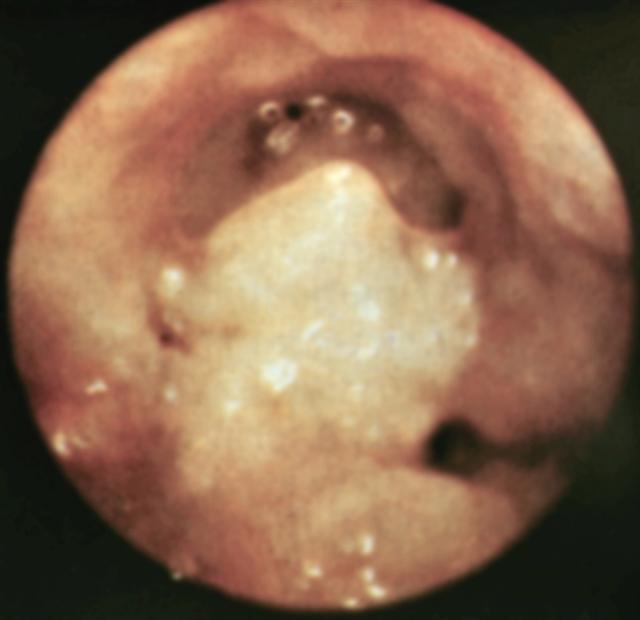

Рис. 11. Гистероскопическая картина при полиповидном раке тела матки.